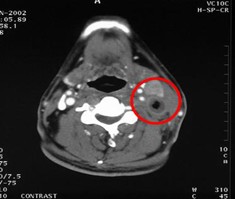

男,60岁,鼻咽癌Ⅲ 期,T2N2M0,治疗前肿瘤充满鼻咽腔和后鼻腔后缘,23.5cm2。治疗方案:今又生瘤内注射,1×1012VP/次/周,共6周,并联合放疗40Gy。治疗后:肿瘤完全消退。

治疗前

治疗后